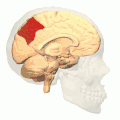

![]() Medial surface of left cerebral hemisphere. (Precuneus visible at top left.) (Anterior to the right.) | |

Medial surface of left cerebral hemisphere. (Precuneus visible at top left.)- Medial surface of left cerebral hemisphere. (Precuneus colored in red.)